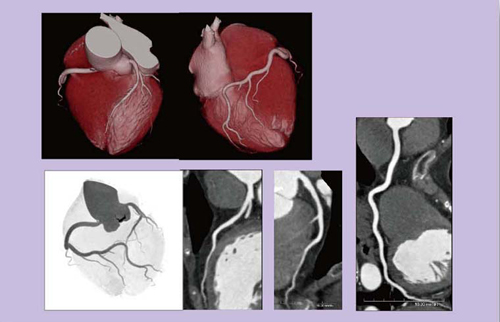

図3は,胸痛の精査で来院した器質的狭窄のない心拍数47bpmの症例で,スキャンタイム0.29秒,被ばく線量は0.97mSvであった。冠動脈が十分評価できており,胸痛のスクリーニングとしても有用と思われる。

図3 68歳,男性,胸痛精査

図4は,ステント留置のフォローアップで,スキャンタイム0.3秒,被ばく線量は1mSvであった。かなり強い石灰化がある症例であったが,ステント内腔が明瞭に描出できている。

図4 74歳,男性,ステント留置フォローアップ